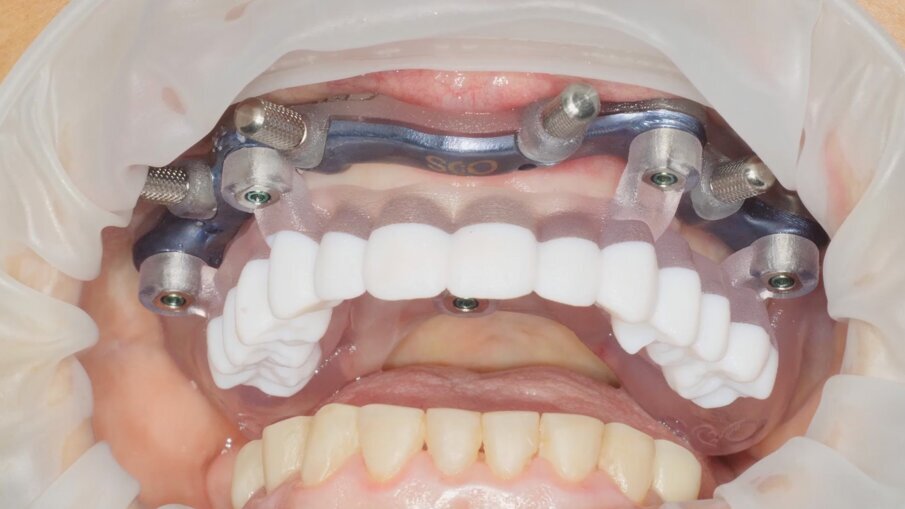

Veniamo quindi al posizionamento della protesi mediante carrier, a sua volta ancorato agli stessi punti di fissaggio della dima base. È significativo osservare come la stabilizzazione della sola vite palatale consenta l’allineamento perfetto tra i sistemi di fissaggio (Fig. 22), mentre il dettaglio mostrato in Fig. 24 illustra efficacemente come prima della cementazione della protesi l’accoppiamento e la centratura del foro protesico appaiano perfetti, confermando quindi come l’obiettivo di alloggiamento della protesi nella sede prestabilita sia stato colto. Per la fase di cementazione con cemento duale si è prestata attenzione alla realizzazione di un foro aggiuntivo per permettere al materiale di raggiungere gli abutment. I fori di accesso alle viti vengono tappati con filo di teflon (Figg. 25, 26) ed è a questo punto possibile andare a fissare la protesi e rimuovere il sistema carrier (Fig. 27). Lasciamo la dima in posizione, così che nell’eventualità in cui un abutment non dovesse essere stato cementato correttamente, ci riserviamo la possibilità di riprendere il posizionamento strategico dell’intero sistema Pcube, intercettando possibili impedimenti alle manovre di finalizzazione del caso.

Nella fase di controllo finale possiamo apprezzare come i rapporti di intercuspidazione programmati siano stati perfettamente rispettati (Fig. 28), senza necessità di ricorrere a procedure di auto-centratura della protesi, grazie ad una attenta pianificazione digitale. Eseguiamo una scansione con scan abutment in posizione prima di procedere con la rimozione della dima base e il fissaggio della protesi (Figg. 29-31). Controlliamo le possibilità di mantenimento igienico tenendo conto che, trattandosi di un intervento flapless, non abbiamo le problematiche legate alla gestione di una linea di incisione (Fig. 32). La Fig. 33 mostra la corretta guarigione dei tessuti quindici giorni dopo il trattamento. Eseguiamo un controllo radiografico mirato a verificare il corretto alloggiamento di tutti gli impianti e della protesi (Fig. 33), dove possiamo vedere la struttura di rinforzo in fibra di vetro.